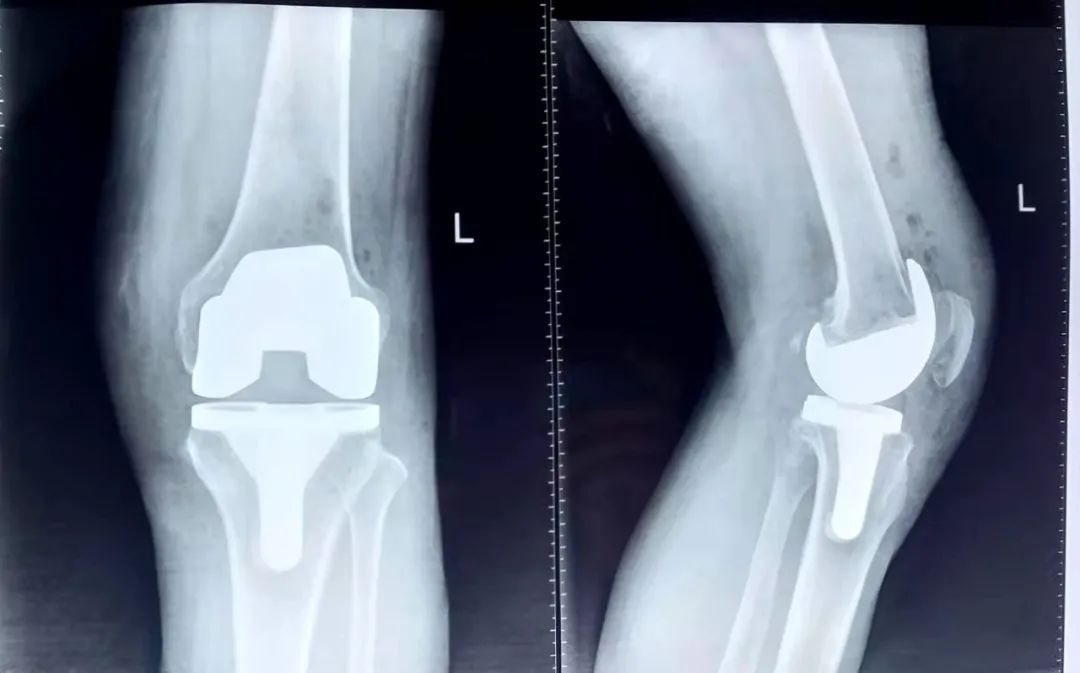

術后影像:

膝關節骨性關節炎的手術治療方法主要有:關節鏡清理、脛骨高位截骨(HTO)、單科置換和全膝關節置換。此病例患者年齡偏大,關節退變嚴重,有屈曲內翻畸形,因此我們選擇了全膝關節置換術,并且堅持微創理念,在手術時控制手術時間和失血量。術后第二天下床行走,預防下肢的靜脈血栓,患者疼痛得到明顯改善,功能恢復良好。